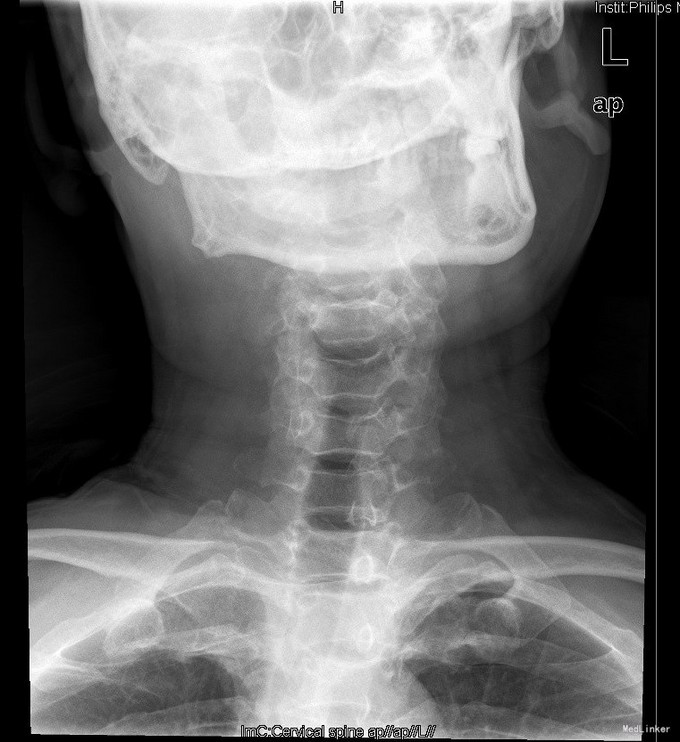

查体:查体:T:36.7oC,P:80次/分,R:20次/分,BP:137/82mmHg。神志清楚,无病容,皮肤巩膜无黄染,全身浅表淋巴结未见肿大。。颈静脉正常。心界正常,心律齐,各瓣膜区未闻及杂音。胸廓未见异常,双肺叩诊呈清音,双肺呼吸音清,未闻及干湿啰音及胸膜摩擦音。腹部外形正常,全腹柔软,无压痛及反跳痛,腹部未触及包块,肝脏肋下未触及,脾脏肋下未触及,双肾未触及。双下肢无水肿。视:平车推入病房,颈椎颈托围领固定,颈部、前额部及全身皮肤未见皮损及异常。触:颈1-4棘突及椎旁明显压痛、叩击痛,感觉正常,四肢肌张力正常。动量:颈椎活动受限,尤以旋转受限为重。双侧肱二头肌反射、肱三头肌反射、膝反射正常,双侧babinski征阴性,右侧Hoffmann征阳性、左侧阴性。 辅助检查:颈椎X线片、MRI、CT提示:寰椎椎板前弓骨折,寰枢关节旋转半脱位

诊断:1.陈旧性寰枢关节旋转脱位2.陈旧性寰椎前弓骨折 治疗:全麻下行:行经前路寰枢椎脱位切开撬拨复位+经后路寰枢椎侧块螺钉内固定、去髂骨后外侧植骨融合术